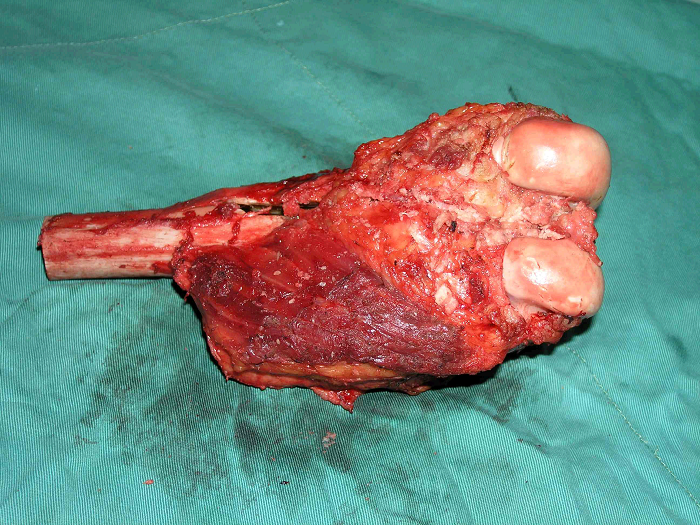

3、病例3:女 25岁 左股骨下端骨旁骨肉瘤,行瘤段广泛切除定制型假体置换术

图 18 肿瘤标本

a:外观象 b:剖面象

图 19 组织学特点:见较成熟的层状结构骨小梁,小梁间为增生的纤维母细胞,细胞有异型。